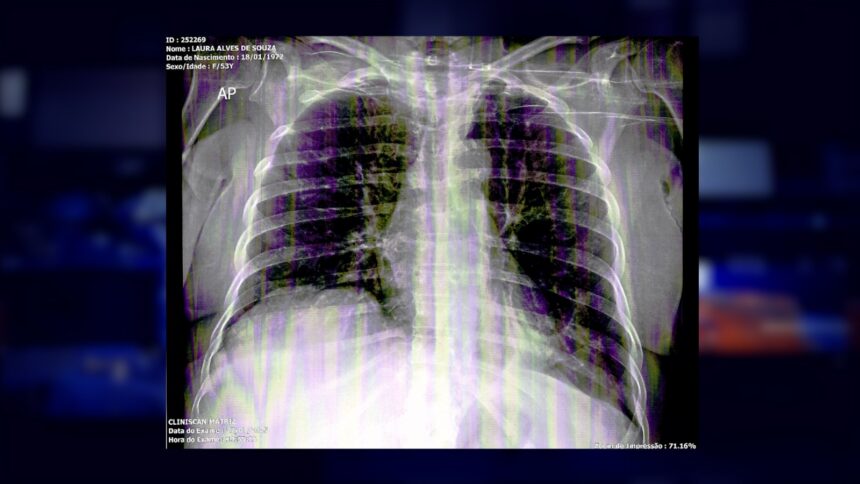

Laura Alves sofreu um grave acidente no dia 28 de maio de 2024. A mulher passou por três cirurgias na coluna no Hospital Geral de Roraima, desde então, enfrenta complicações. Conforme relatado à reportagem da TV Imperial, ela já aguarda há oito meses por uma resposta sobre o pedido de Tratamento Fora de Domicílio (TFD), necessário para realizar uma operação que não é feita em Roraima.

Laura afirma que precisa colocar uma placa na coluna, o que permitiria que ela sentasse em uma cadeira de rodas. “Essa cirurgia não é para eu andar, é só para eu sentar […] Não levanto da cama, porque eu não posso sentar, não posso me movimentar”, relatou a mulher.